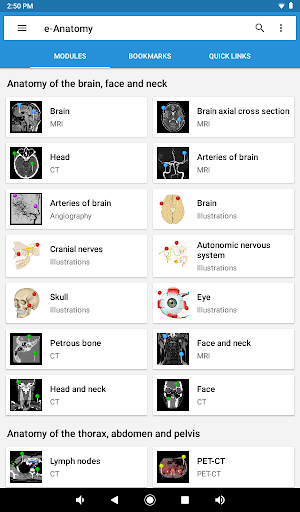

IMAIOS e-Anatomy es un atlas de anatomía humana para médicos, radiólogos, estudiantes de medicina y técnicos en radiología. Echa un vistazo a más de 26 000 imágenes médicas y anatómicas de forma gratuita antes de suscribirte a nuestro detallado atlas de anatomía humana.

e-Anatomy se basa en el galardonado atlas en línea IMAIOS e-Anatomy. Lleva contigo la referencia más completa de anatomía humana, dondequiera que vayas, en tu dispositivo móvil o tableta.

e-Anatomy tiene más de 26 000 imágenes que contienen series de imágenes en vistas axiales, coronales y sagitales, así como radiografías, angiografías, imágenes de disección, gráficos anatómicos e ilustraciones. Todas las imágenes médicas fueron etiquetadas cuidadosamente, más de 967 000 etiquetas disponibles en 12 idiomas, incluida la Terminologia Anatomica latina.